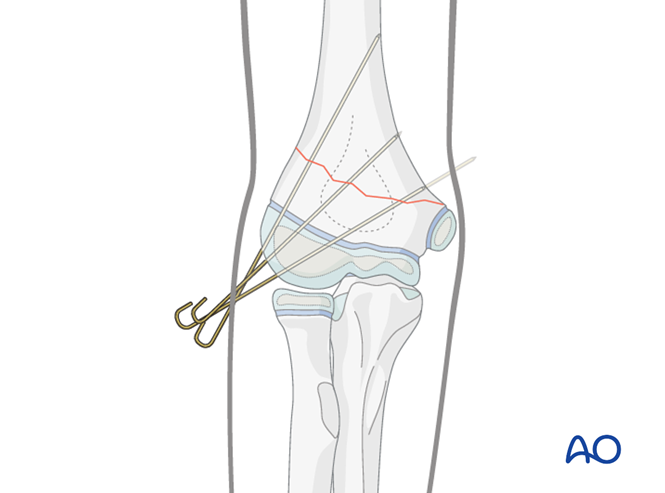

一,儿童骨化中心